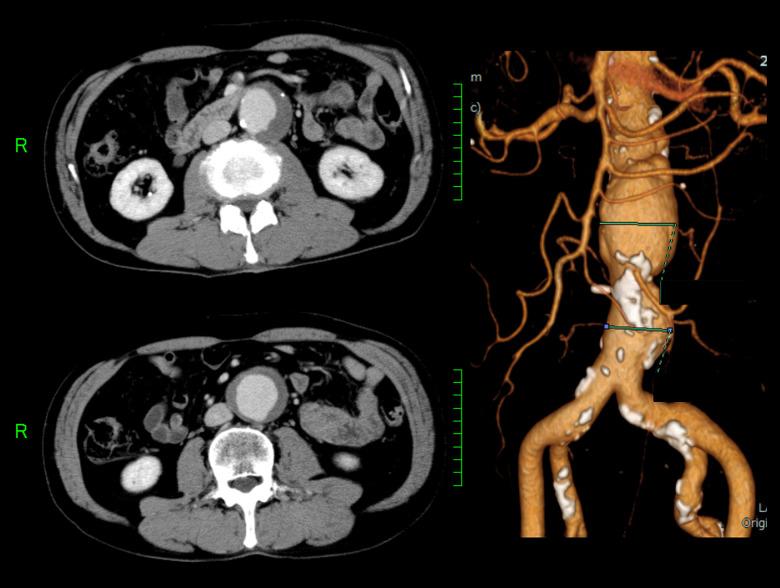

BACKGROUND Isolated superior mesenteric artery dissection (SMAD) is a rare vascular disease that is difficult to diagnose. We report a case of SMAD in a patient with an abdominal aortic aneurysm (AAA) that mimicked an impending rupture of the AAA. In addition, we describe several clinical biases that contributed to the delayed diagnosis. CASE REPORT A 66-year-old man presented with a 3-day history of abdominal pain, without a history of trauma, that worsened gradually and caused him to visit our hospital. The patient's medical history included an AAA under observation. The patient was well oriented and initially remained hemodynamically stable, and the abdomen was soft and non-tender on palpation. An emergency contrast-enhanced computed tomography (CT) scan confirmed a 44-mm AAA without any leakage, but with an isolated SMAD. His previous physician confirmed there was no change in the AAA size since 3 months prior to hospital admission. Thus, the symptoms were caused by the isolated SMAD. The patient showed improvement with pain-relieving and antihypertensive management, without anticoagulation therapy or revascularization, and was discharged on day 25 of admission without any complications. CONCLUSIONS The misdiagnosis in this case was attributable to several clinical biases, including search satisfaction, Sutton's slip, and anchoring bias. Physicians should guard against presumptive diagnoses based on patient symptoms or initial plausible findings and instead pursue a thorough workup to reach a definitive diagnosis.

背景 孤立性肠系膜上动脉夹层(SMAD)是一种罕见的血管疾病,诊断困难。我们报告一例患有腹主动脉瘤(AAA)的患者发生SMAD,其表现类似AAA即将破裂。此外,我们描述了导致诊断延迟的几种临床偏差。病例报告 一名66岁男性,有3天腹痛病史,无外伤史,疼痛逐渐加重,遂来我院就诊。患者病史包括正在观察中的AAA。患者定向力良好,最初血流动力学稳定,腹部触诊柔软无压痛。急诊增强计算机断层扫描(CT)证实有一个44毫米的AAA,无任何渗漏,但存在孤立性SMAD。其之前的医生证实自入院前3个月以来AAA大小无变化。因此,症状由孤立性SMAD引起。患者经止痛和降压治疗后病情改善,未进行抗凝治疗或血管重建,入院第25天出院,无任何并发症。结论 该病例的误诊归因于几种临床偏差,包括搜索满足感、萨顿疏忽和锚定偏差。医生应警惕基于患者症状或最初似是而非的发现进行推定诊断,而应进行全面检查以得出明确诊断。